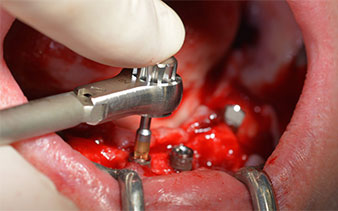

Dopo aver rimosso la dentatura residua dalla mandibola, la cresta alveolare viene esposta da 37 a 47.

Prima di tutto, è stato individuato il forame mentoniero come limite della struttura anatomica. Successivamente, l'osso corticale della cresta è stato lisciato con un manipolo e una fresa larga a rosetta (Fig. 4).

dentatura residua

Fig. 4